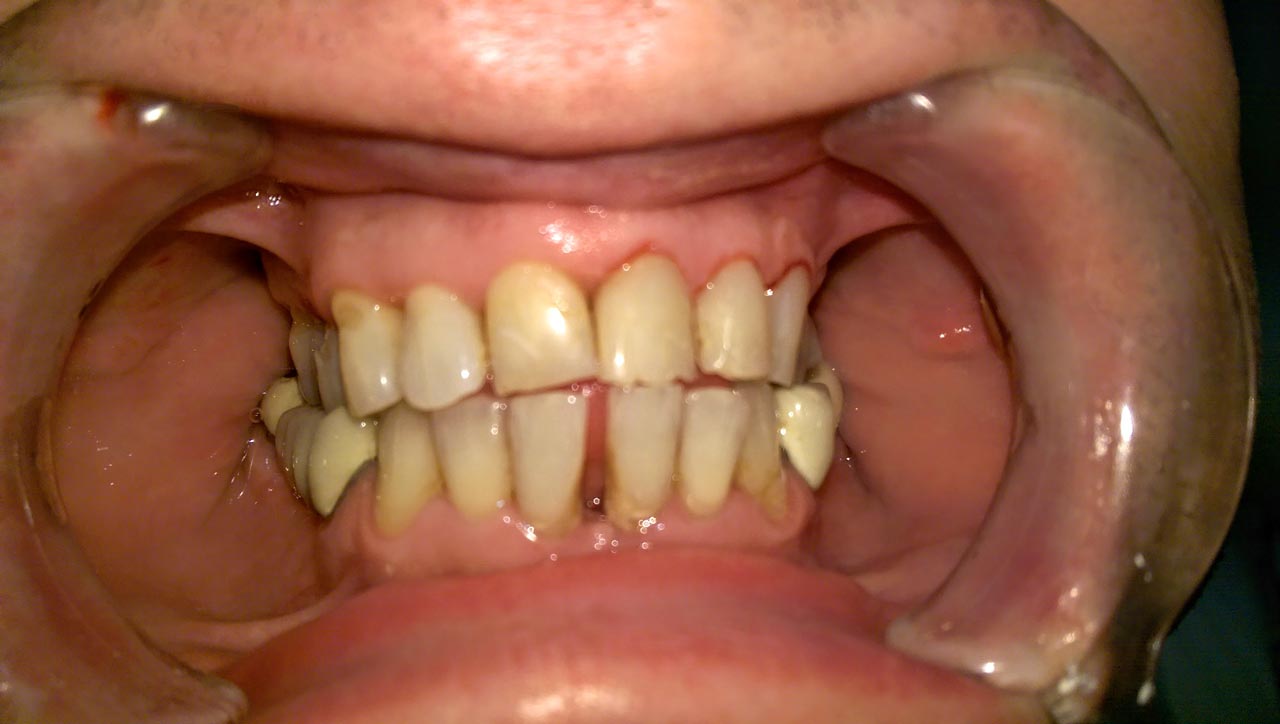

Elhanyagolt fogsor cseréje 2 nap alatt

2 nap alatt varázsoltuk ezt a szép esztétikus alsó, felső körhídat implantátumokkal megtámasztva a korábban elhanyagolt szájba. Az 1. nap 26 fogat távolítottunk el, mert annyira rossz állapotban voltak, és rögtön azonnal terhelhető IHDE svájci implantátumokat raktunk be, fentre 8, lentre 6 darabot. A sebeket összevarrtuk és intraorális szkennerrel digitális lenyomatot vettünk. 2 nap múlva pedig beragasztottuk a kész PMMA műanyag körhidakat. Dr. Kelemen Péter és a Symbion Fogtechnika munkája.